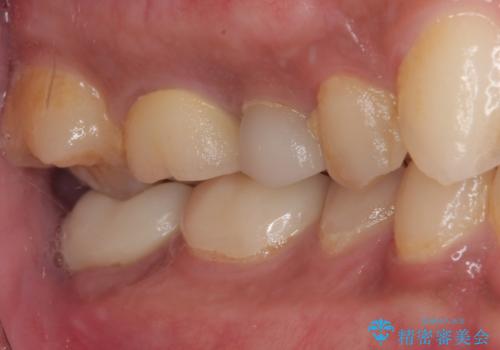

セラミックが欠けた オールセラミッククラウン

- セラミックが欠けたとのことで来院された患者様です。新しくセラミックを作り直していく治療計画としました。

拡大鏡視野下で、セラミックの被せもの、虫歯の除去を行い、オールセラミッククラウンに適した形に整えました。

見た目、機能面ともに満足していただけました。

咬み合わせが強く以前のセラミックを割ってしまっているので就寝時にはナイトガードを使ってもらう予定です。